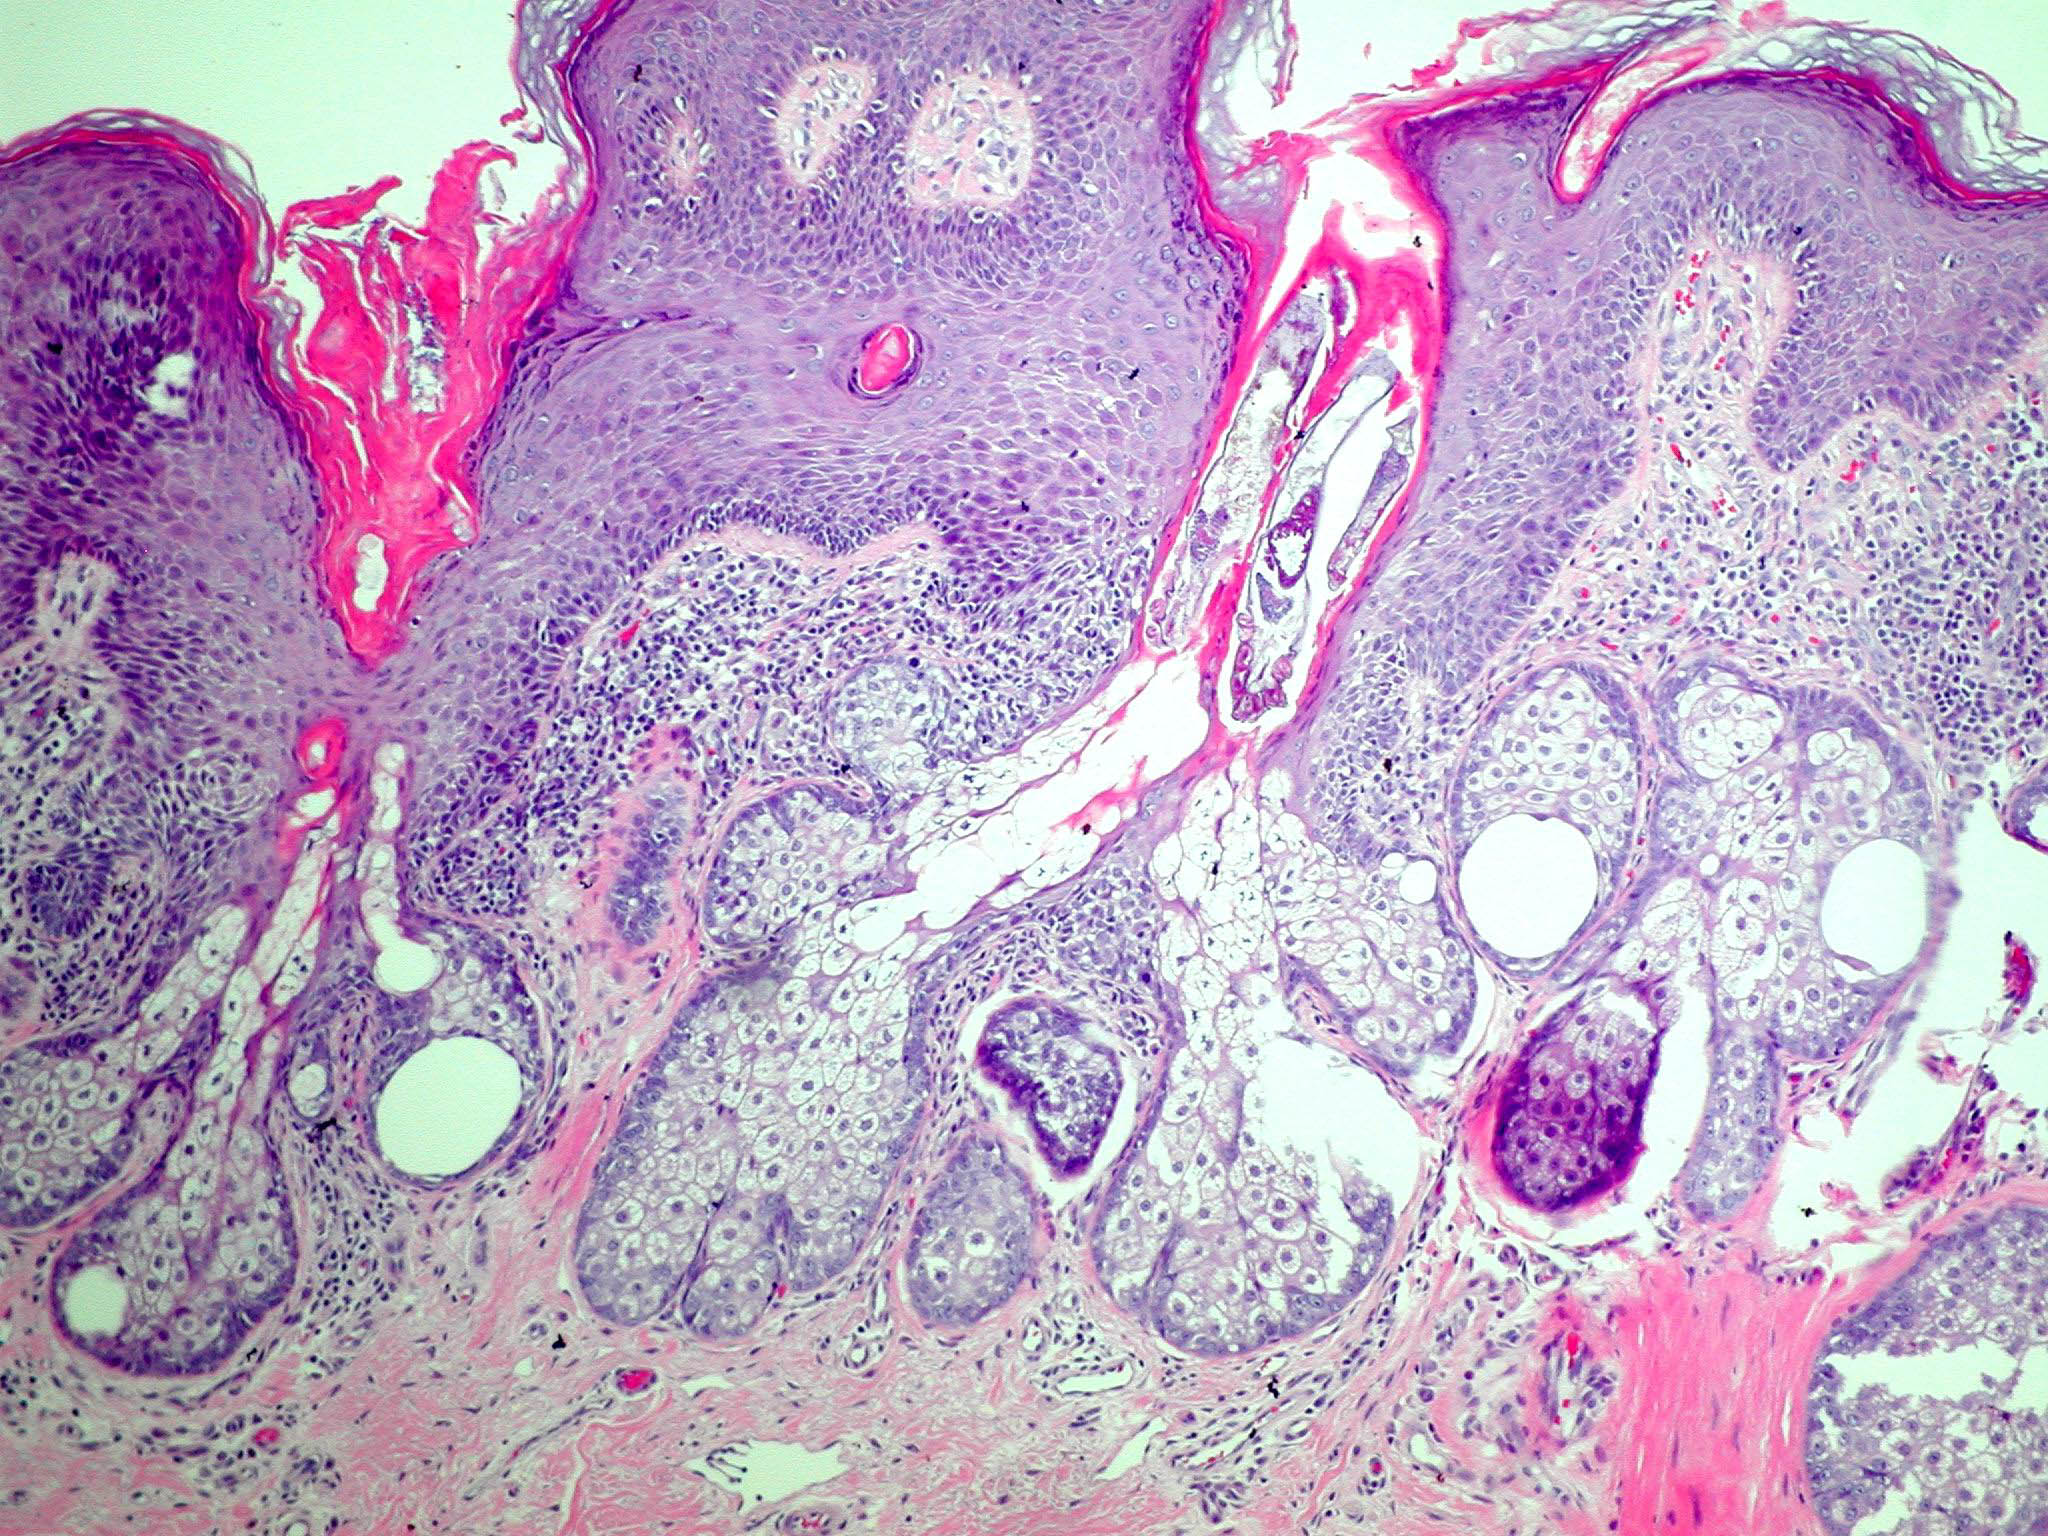

Nevus_sebaceous = الوحمة الدهنية